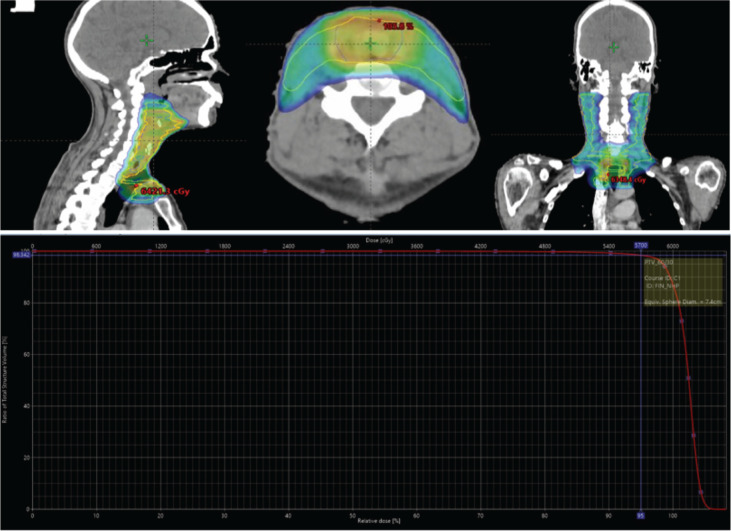

Case presentation: We present a case of a 59-year-old male who presented with hoarseness of voice and acute onset of respiratory distress. Post emergency tracheostomy for respiratory distress, evaluation with contrast-enhanced computed tomography head and neck revealed cT3N0M0 supraglottic disease. Biopsy revealed poorly differentiated carcinoma. In view of thyroid cartilage erosion, the patient underwent two cycles of neo-adjuvant chemotherapy followed by total laryngectomy, bilateral neck dissection and primary closure. Postoperative histopathology revealed ypT1N0 LEC, with adequate margins and adequate neck dissection. The patient was then treated with adjuvant chemoradiotherapy. 6 months follow-up positron emission tomography/computed comography shows no locoregional disease.